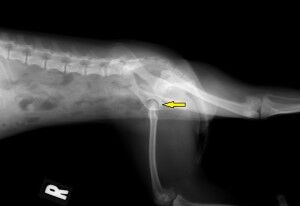

その結果が下の写真です。

わかりにくいのですが、左の写真 中央部に股関節(骨盤と大腿骨が接している

部分の関節)に隙間 (黄色矢印) があります。普通はもっと狭いのですが、症例はかなり広く

なっています。この画像からレッグペルテスと判断しました。この関節は放っておくと

どんどんひどくなり、患肢を使わなくなっていきます。現に右の写真で、右脚の大腿部の

筋肉が細くなっています(黄色矢印)ので、あまりこの脚をあまり使っていないため

筋肉が萎縮し始めています。治療が遅れると、治療後も脚を使わなくなってしまうことが

あります。